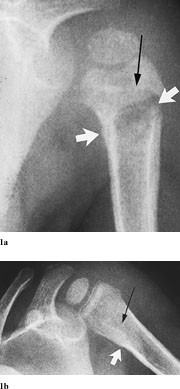

Pasient 1. En 14 måneder gammel gutt hadde smerter i venstre ankel og skulder, var ved innleggelsen afebril og i god allmenntilstand. Det var nedsatt aktiv bevegelse i ankel og skulder. Innkomstprøver viste CRP 58, leukocytter 16,2, hvorav 4,8 nøytrofile granulocytter. Røntgen av underarm indikerte fraktur gjennom proksimale del av humerusskaftet. Røntgen totalskjelett viste ikke andre frakturer. Skjelettscintigrafi seks dager etter avkreftet diagnosen akutt osteomyelitt, og han fikk derfor ingen behandling. To uker senere viste røntgen av venstre arm (fig 1) osteolytiske oppklaringer i proksimale, venstre humerus, oppfattet som mulig osteomyelitt eller tumor. Han var fortsatt afebril, men i noe redusert allmenntilstand, og venstre arm virket smertefull ved berøring. CRP var 40, leukocytter 12,9, hvorav 7,5 lymfocytter, og SR 104. Blodkultur og aspirat fra humerus gav ikke oppvekst av bakterier. Intravenøs antibiotikabehandling ble startet. MR av overarmen (fig 2) viste destruksjon i beinmarg med sentral nekrose i humerusmetafysen, oppfattet som sannsynlig osteomyelitt. Skjelettscintigrafi viste intet sikkert patologisk. Klinisk ble han gradvis bedre.

Røntgenkontroll etter 13 dagers behandling viste økende beintetthet i det aktuelle området uten tegn til nye osteolytiske områder. MR-kontroll etter tre ukers behandling viste klar bedring. Etter tre måneder hadde han full bevegelighet i skulderen.